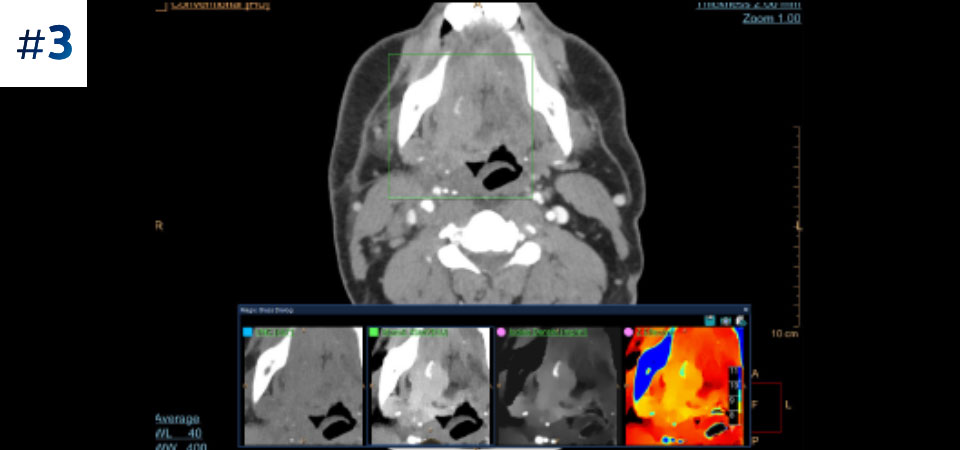

Masse cervicale

Observez la différence entre le scanner à détection spectrale et le scanner classique

Découvrez les avantages du scanner à détection spectrale